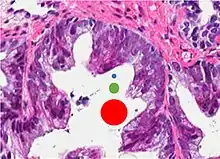

77%[notes 2] | 54%[notes 2] | ![]() |

Further information in section below

|

Tumorous glands: | As usual |